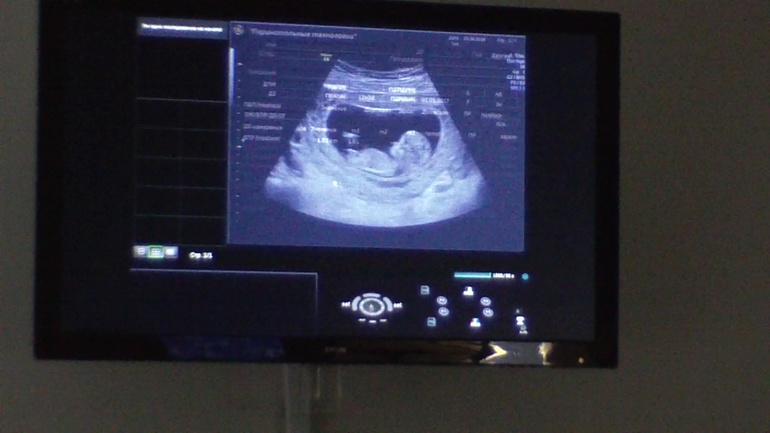

Наш первый скрининг)

Результаты: УЗИ, КТГ, доплера, скринингаСходили мы в субботу на скрининг)взяли с собой видеокамеру и все сняли,на память)))В итоге врач сказал,что с малышом все в порядке) КТР 55 мм, ТВП 1,1 ЧСС 157 ударов )))срок 12,3 нед))) и фоточка,сами сделали с видео)))